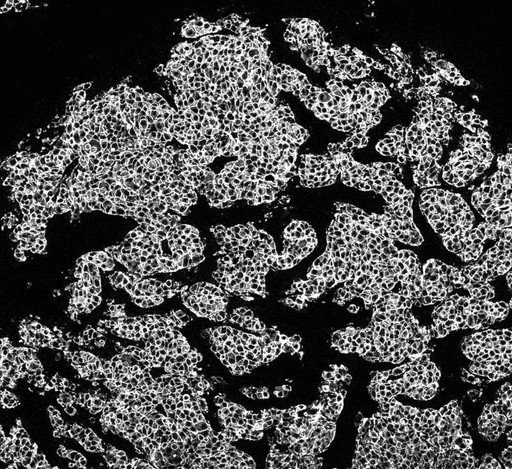

Bo Holmqvist (CSO, Imagene-iT AB) har analyserat de senaste resultaten från Lumitos inmärkningar av nya bröstcancervävnader, av olika grader av HER2 uttryck, som visualiserats med Lumitos UCNP (up-converting nano particles). Samma vävnad har även märkts in på traditionellt sätt, det vill säga med teknik som i dag analyseras av histologer och kliniska patologer (DAB-reagens), för jämförelser. Bilddokumentationen av UCNP teknologin är genererad i Lumitos scanner som sedan bedömts av histolog/patolog via Sectras miljö Pacs on Demand mjukvara.

| – Jag anser att Lumitos bildmaterial håller en histologiskt och inmärkningsmässigt hög kvalitet. Lumitos bilder ger förbättrade möjligheter för den histopatologiska bedömningen. Dessutom, utifrån bilddokumentering med bra bildkvalitet kan en digital bedömning av bildmaterialet ge ytterligare stöd till den visuella kliniska bedömningen, säger Bo Holmqvist. | |

Bo Holmqvist menar att kvaliteten i dag, för Lumitos bilddokumentation visar goda förutsättningar för att även kunna implementera en mjukvara för digital kvantifiering och bedömning. Det kan då bli enklare, och även säkrare, att göra en bedömning baserad på denna mjukvara i kombination med den visuella bedömningen av det digitala vävnadssnittet, inmärkt med Lumitos UCNP med hög bildkvalitet. Patologen

och forskaren skulle kunna se på bilderna och ladda dem i en mjukvara för digital kvantifiering. Den digitala läsningen kan ge stöd vid svåra graderingar av inmärkningar – men även för att kunna sortera ut fall som inte behöver analyseras vidare, vilket sparar resurser.

Lumitos teknologi gör det möjligt att detektera specifika markörer för tex cancer med nano-partikelbaserade reagenser, vilka ger en specifik och hög inmärkningsintensitet och därmed ger hög kvalitet vid bilddetektion.

Gradering av cancer, det vill säga skillnader i inmärkning för att ställa rätt diagnos, ställer extra höga krav och är i dag en subjektiv visuell bedömning, vilken kan variera beroende på laboratoriets inmärkningskvalitet och bedömande individ.